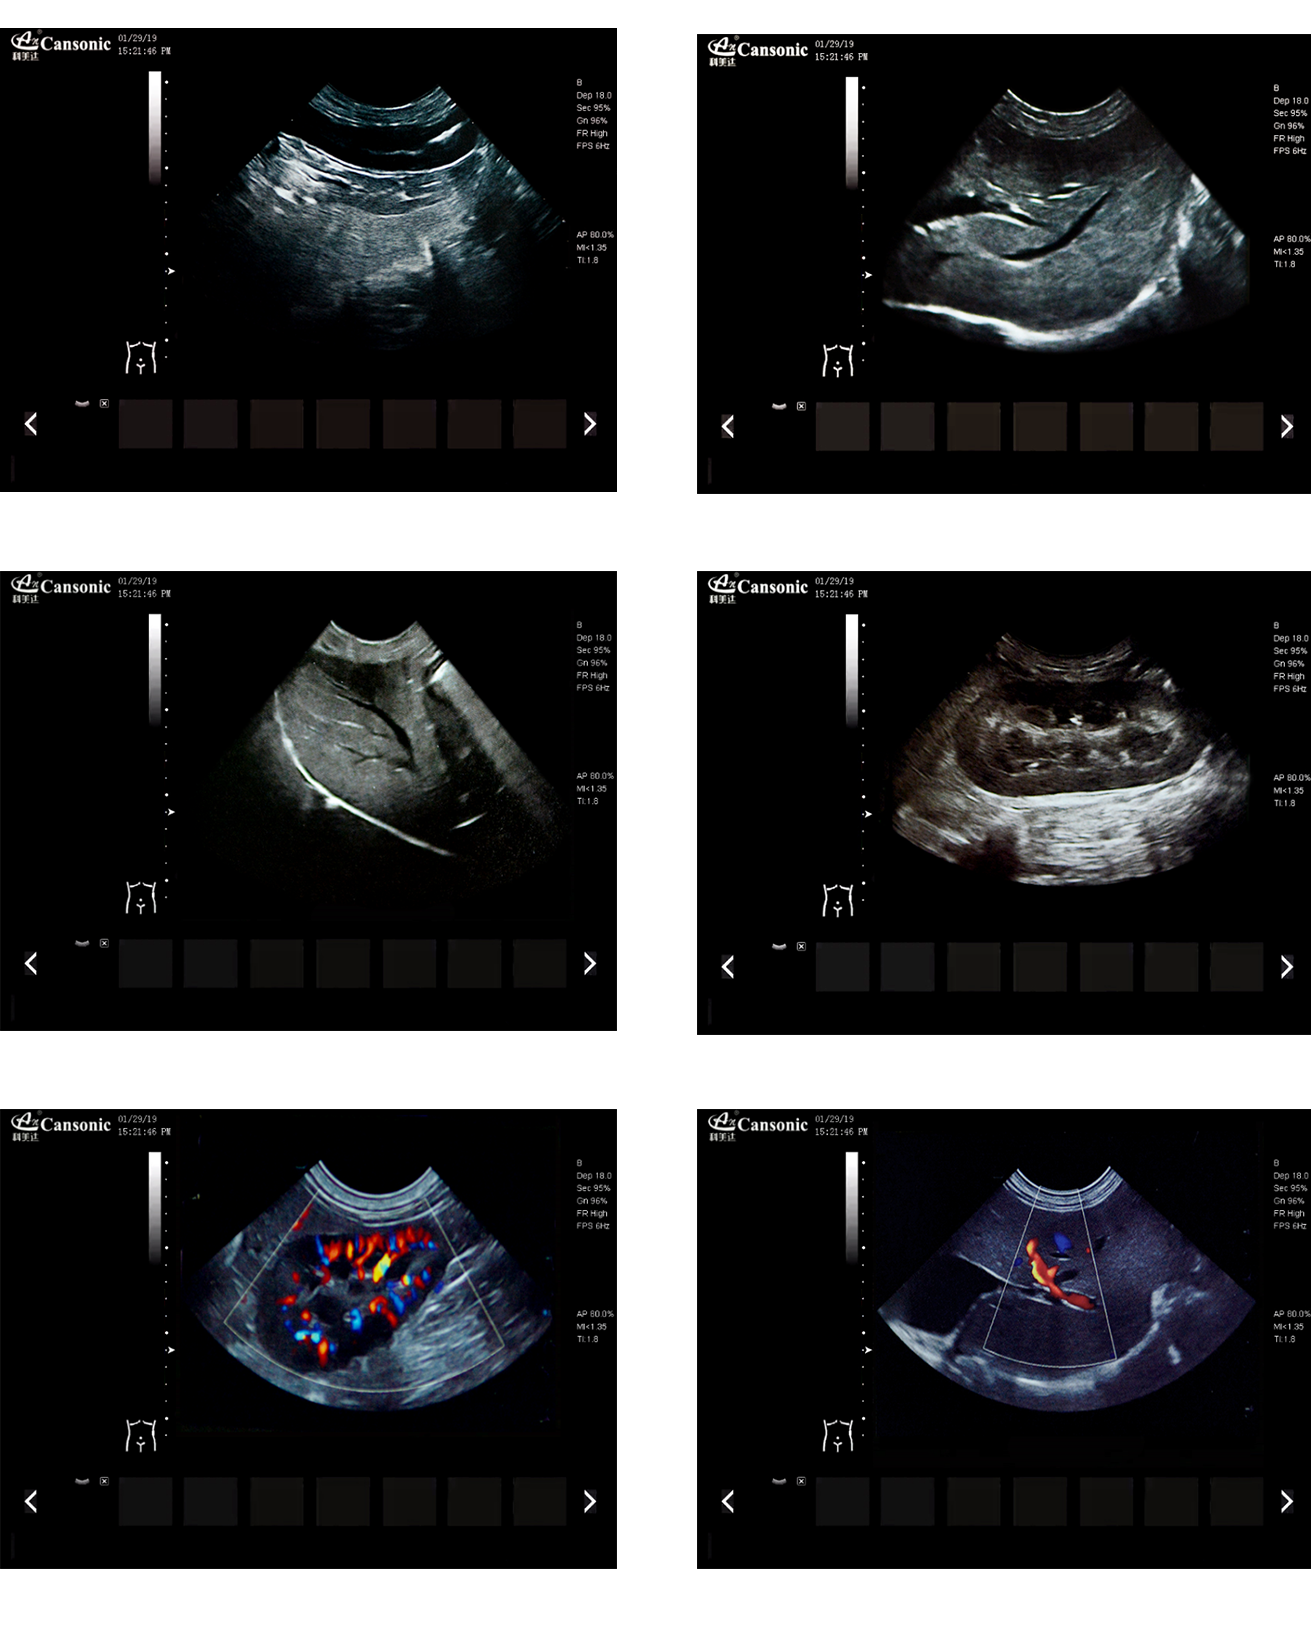

K2V

產(chǎn)品特點:

1、薈萃前沿成像技術(shù),實現(xiàn)高精與靈便的完美融合,提供完整的動物彩超診療方案

2、專業(yè)的獸用測量軟件,簡捷的工作流,適合犬、貓、馬、牛、羊等 各類大小動物

3、iClear斑點噪聲抑制抑制噪聲干擾,使動物組織結(jié)構(gòu)更清晰

4、具有廣泛的動態(tài)范圍,顯示出色的組織均勻性,減少了偽影及噪聲

5、精細(xì)血流識別技術(shù),增加了可疑病變更多的信息分析

6、先進的算法帶來清晰的穿刺針顯示,降低穿刺活檢操作難度

7、圖像優(yōu)異,同時性能穩(wěn)定,每天能進行大量的動物超聲檢查

8、輕巧的機身,耐摩損的把手,適應(yīng)各種復(fù)雜的動物使用環(huán)境

臨床圖示